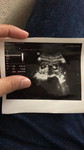

Dreaming of becoming a parent

ĐồngDreaming of becoming a parent